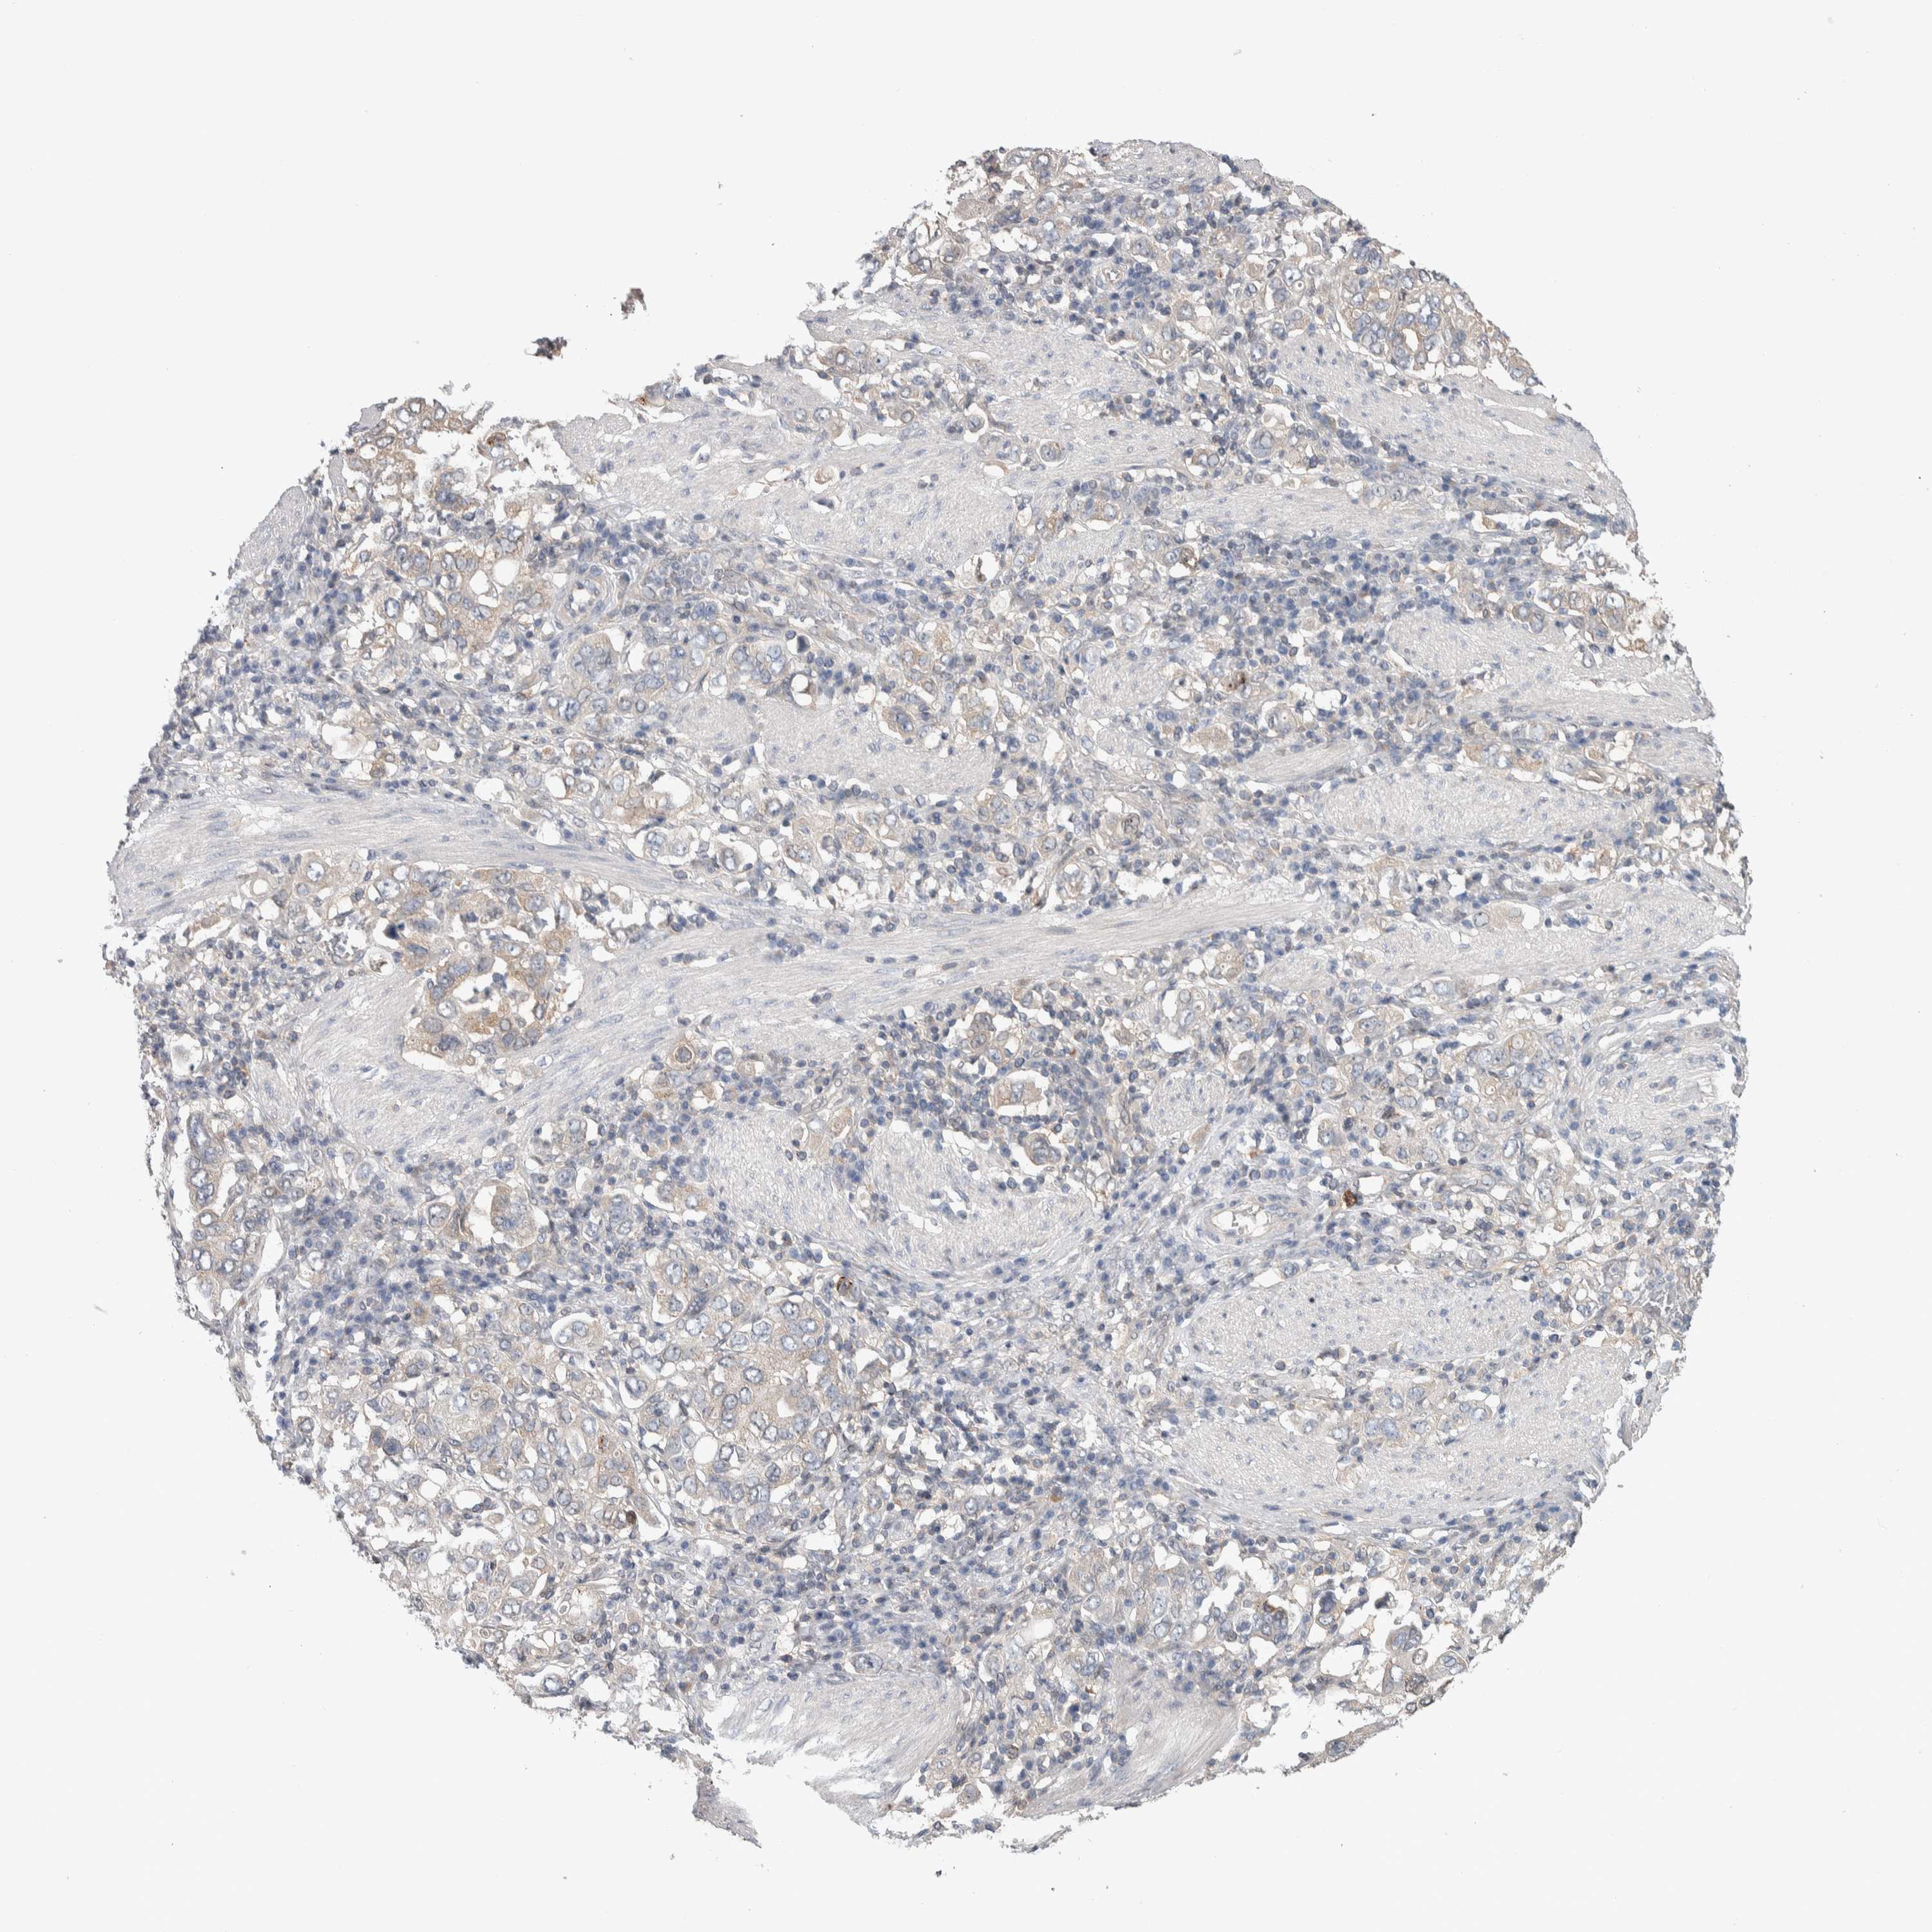

STOMACH CANCER - Protein expressioni

A mouse-over function shows sample information and annotation data. Click on an image to view it in a full screen mode. Samples can be filtered based on level of antibody staining by selecting one or several of the following categories: high, medium, low and not detected. The assay and annotation is described here.

Antibody stainingi

Antibody staining in the annotated cell types in the current human tissue is reported as not detected, low, medium, or high, based on conventional immunohistochemistry profiling in selected tissues. This score is based on the combination of the staining intensity and fraction of stained cells.

Each image is clickable and will lead to virtual microscopy that enables deeper exploration of all samples and also displays staining intensity scores, fraction scores and subcellular localization as well as patient and tissue information for each sample.

Antibody HPA024432

Staining

High

Medium

Low

Not detected

Intensity

Strong

Moderate

Weak

Negative

Quantity

>75%

75%-25%

<25%

None

Location

Nuclear

Cytoplasmic/membranous

Cytoplasmic/membranous,nuclear

Adenocarcinoma, NOS